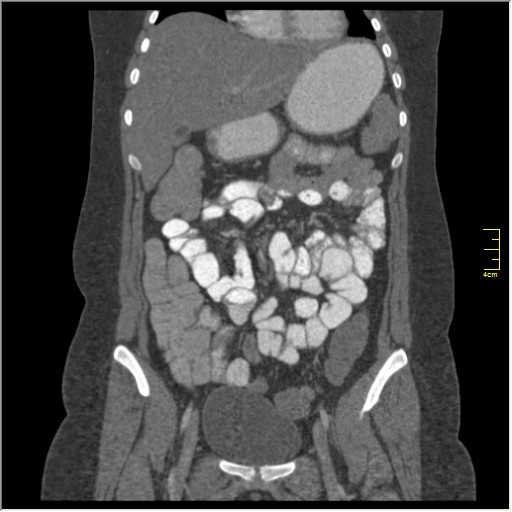

Демонстрационные изображение, оцените возможности метода! Толщина среза реконструкции 0.5-1 мм.